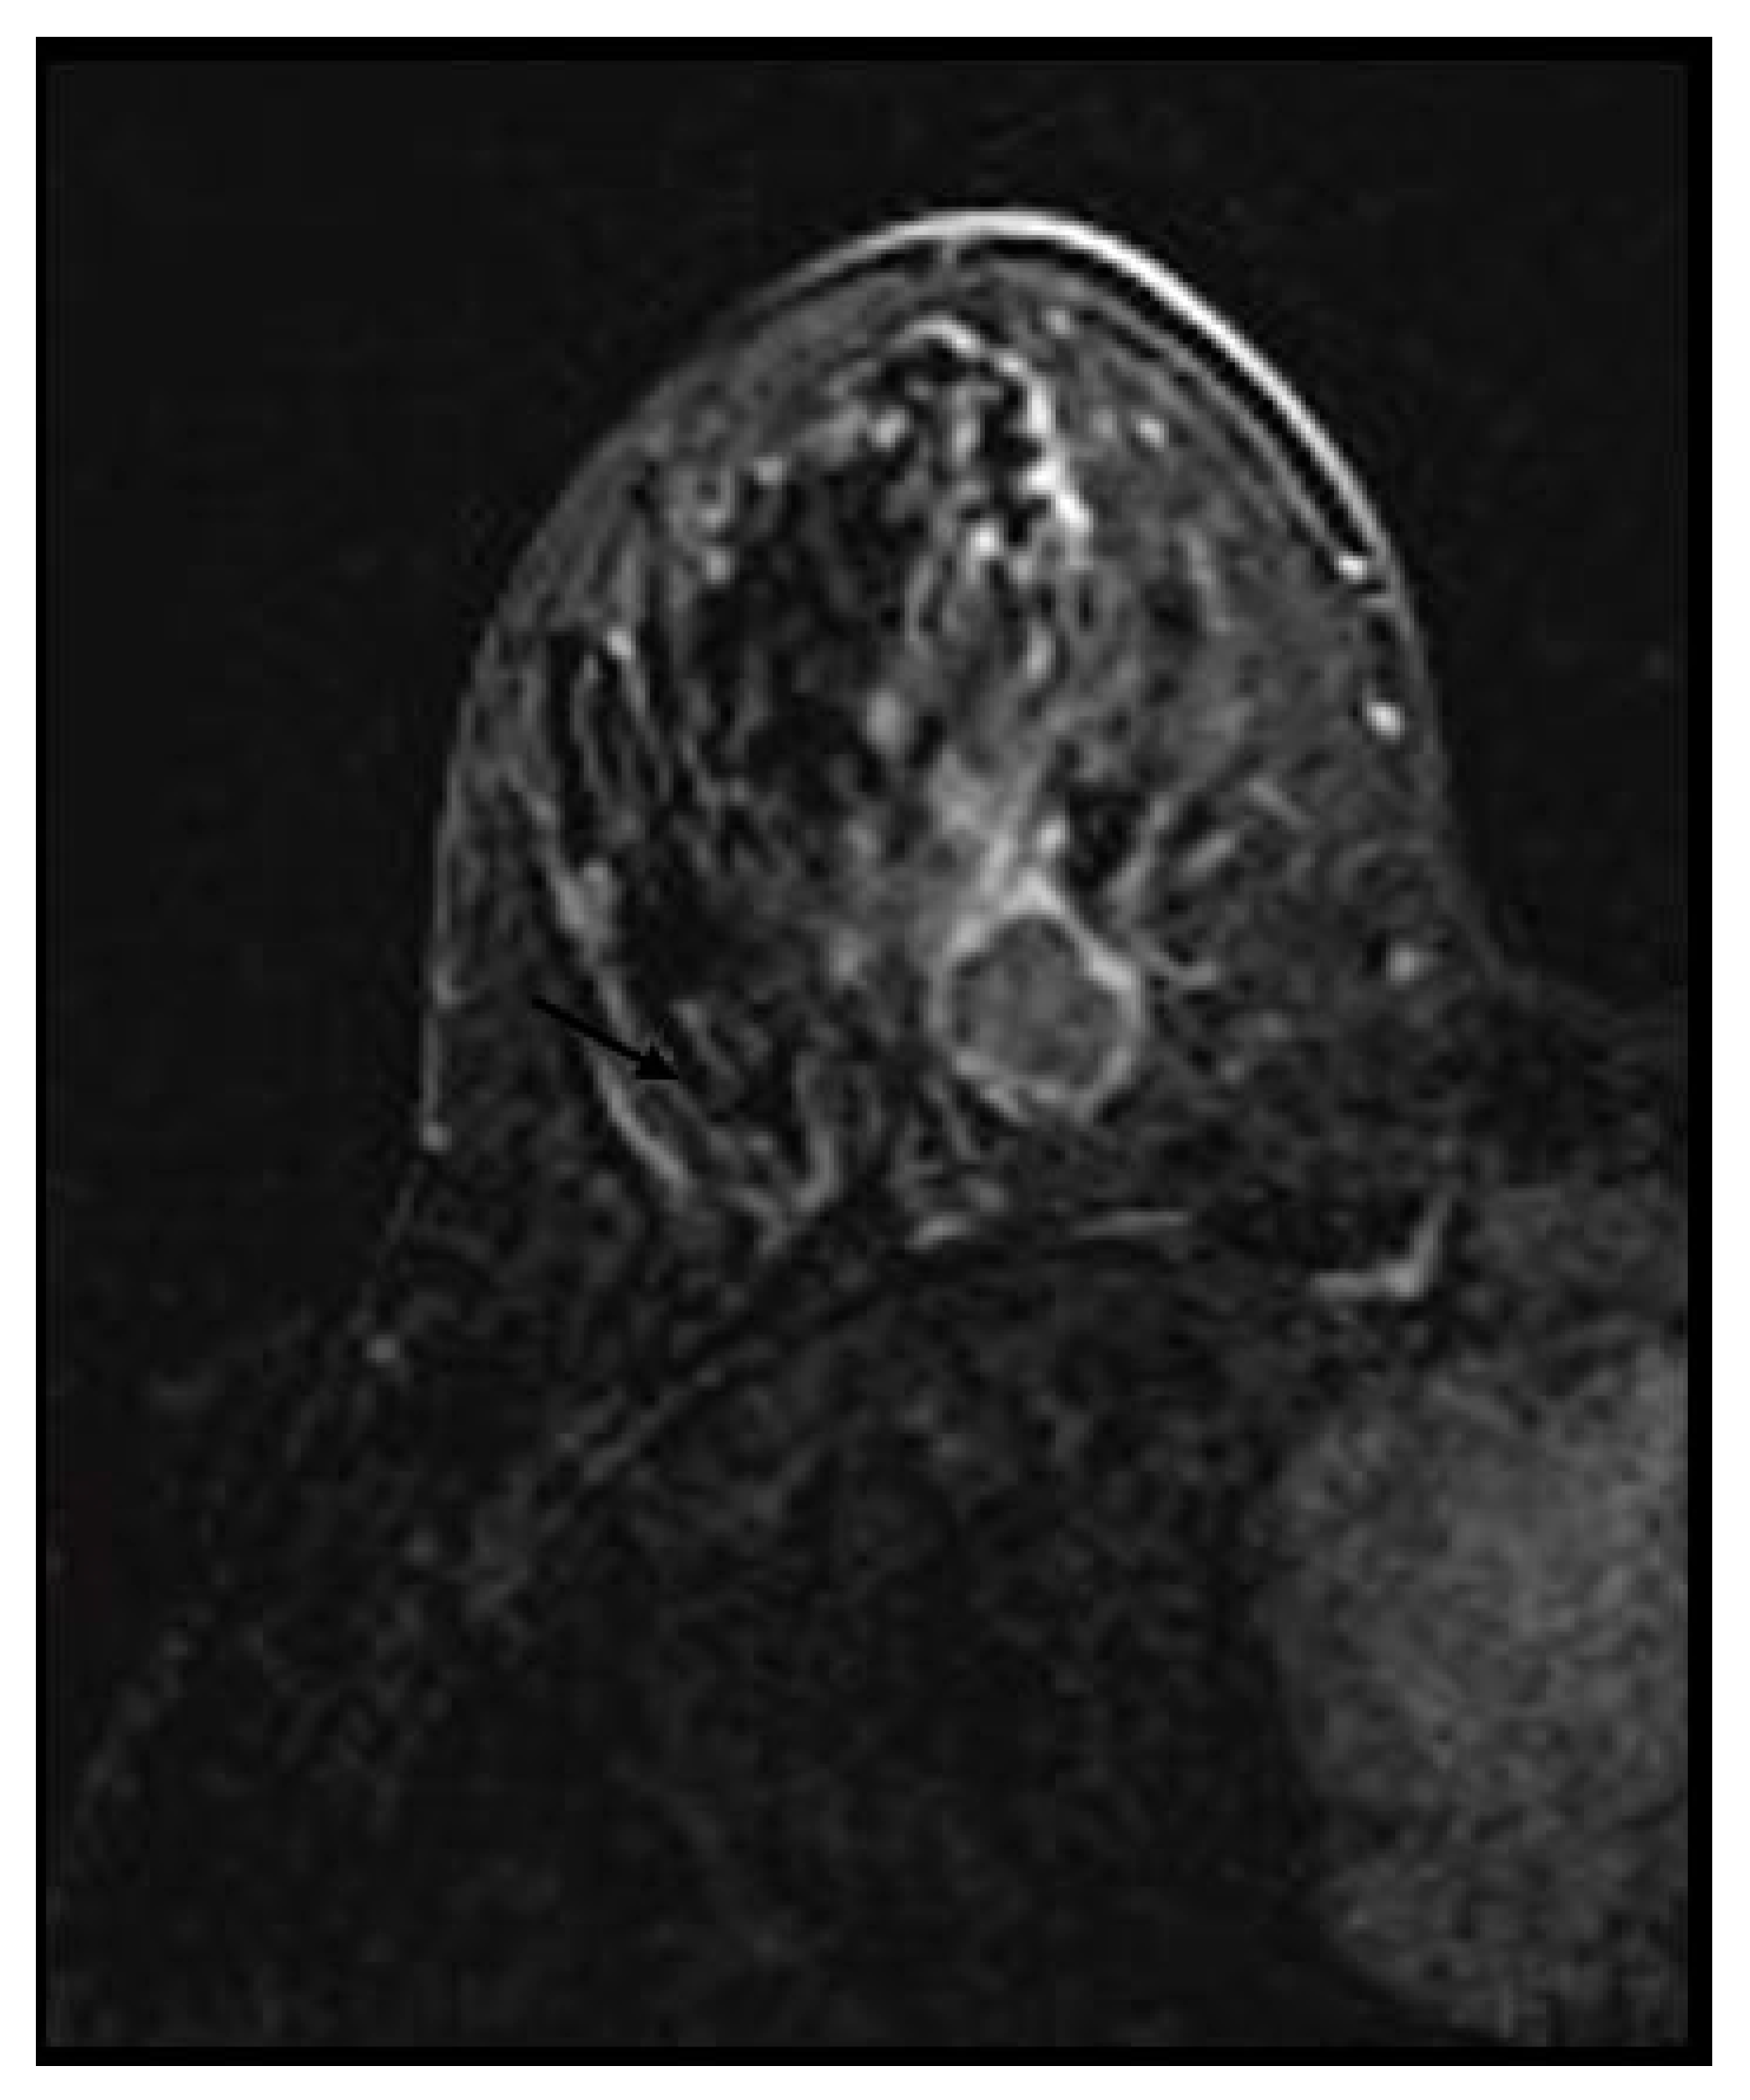

Picture Frame Enhancement Breast Mri . Web the morphologic features, internal enhancement patterns, and limitations of kinetic curves in normal but. Web more peripheral enhancement, or “picture framing,” can also be seen (fig. Web the morphology and temporal degree of enhancement of pathologic breast tissue relative to normal breast tissue. 3) and has been attributed to the arterial. Web it has long been known that normal fibroglandular breast tissue on mri can enhance at variable levels after the.

Web the morphology and temporal degree of enhancement of pathologic breast tissue relative to normal breast tissue. 3) and has been attributed to the arterial. Web it has long been known that normal fibroglandular breast tissue on mri can enhance at variable levels after the. Web the morphologic features, internal enhancement patterns, and limitations of kinetic curves in normal but. Web more peripheral enhancement, or “picture framing,” can also be seen (fig.